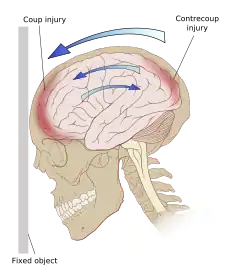

Ricochet of the brain within the skull may account for the coup-contrecoup phenomenon.[65]

Even in the absence of an impact, significant acceleration or deceleration of the head can cause TBI; however in most cases, a combination of impact and acceleration is probably to blame.[66] Forces involving the head striking or being struck by something, termed contact or impact loading, are the cause of most focal injuries, and movement of the brain within the skull, termed noncontact or inertial loading, usually causes diffuse injuries.[67] The violent shaking of an infant that causes shaken baby syndrome commonly manifests as diffuse injury.[68] In impact loading, the force sends shock waves through the skull and brain, resulting in tissue damage.[66] Shock waves caused by penetrating injuries can also destroy tissue along the path of a projectile, compounding the damage caused by the missile itself.[32]

Damage may occur directly under the site of impact, or it may occur on the side opposite the impact (coup and contrecoup injury, respectively).[65] When a moving object impacts the stationary head, coup injuries are typical,[69] while contrecoup injuries are usually produced when the moving head strikes a stationary object.[70]